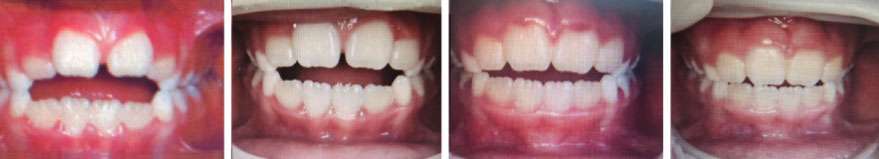

The 9-year-old female patient, presented with an open bite (Figure 1A), a narrow, high palate (Figure 1B) and limited range of mouth opening (Figure 1C). She wanted to eliminate the habit of persistent thumb sucking that she found embarrassing. The patient was started on MyoBrace appliance and was undergoing chiropractic care. The patient was unable to keep the MyoBrace in most of the night. The patient’s mother attempted mouth taping, but the patient often pulled the tape off in her sleep. While the patient was improving, she hit a plateau and the progress slowed down. During that time the patient was diagnosed, by Dr. Riek, to have a posterior tongue-tie.

Post-frenectomy, the patient now easily retains the MyoBrace appliance in the mouth without the need to tape. She no longer sucks on her thumb. Post-frenectomy, a significant progress was observed in both the palate shape and the bite – see sequences in Figures 1A and 1B.